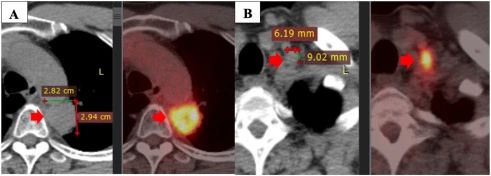

盡管如此,該疾病在 2020 年 5 月繼續發展。PET/CT 掃描顯示原發性腫瘤大小為 28×29 mm,最大標準化攝取值(SUVmax)為 11.2,粘附在縱隔胸膜和主動脈上。此外,左側鎖骨上淋巴結的大小為 9×6 mm,左側門靜脈的一些小淋巴結大小小于 10 mm。

注:一線治療一年后疾病進展:原發性腫瘤(A),左鎖骨上淋巴結(B)。

PD-L1 表達陽性(25%),接受了四個周期的 Alimta(500mgx2)、卡鉑(150mgx2450mgx1)和 Cresida(4mlx2)的二線治療。然而,在 2020 年 6 月的 PET/CT 掃描中,他的病情似乎不穩定。由于疾病的進展,病人的治療計劃發生了變化。